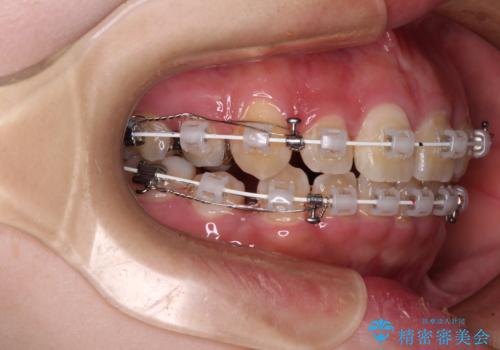

- 審美装置

- 1年7ヶ月

スペースを閉じるステージでの移動がとても早く、1年半ほどで終えることができました。

唇が引っかかる感触もなくなり、口が閉じやすくなりました。